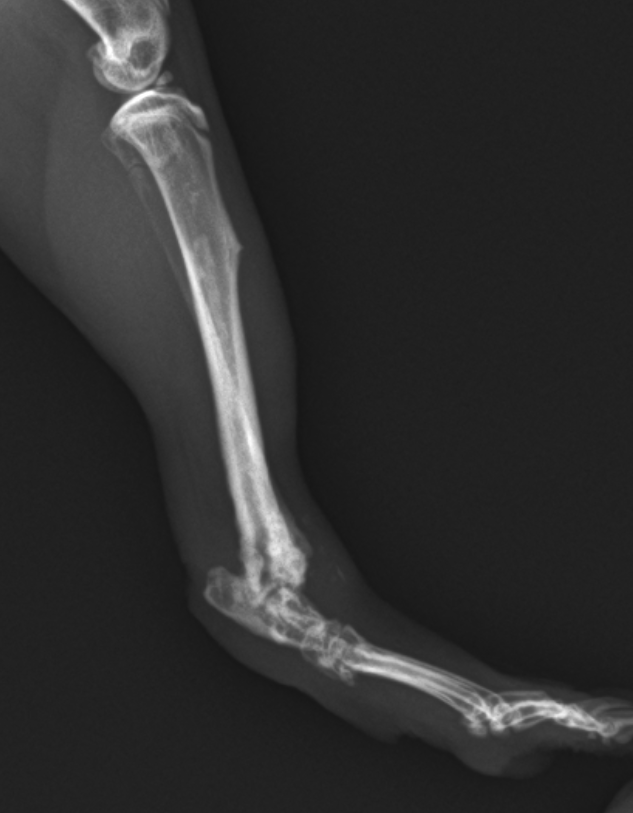

モルモットが後肢をかばっている(後肢:脛骨の骨折) 公開済み: 2024年11月12日更新: 2025年11月2日作成者: koizumi-nest モルモットの骨折は、特に後肢の脛骨(すねの部分)においてよく発生します。 特に若いモルちゃんによく見られるように感じられます。 骨折の仕方によって、手術による整復と固定を実施する必要があります。 モルモットの脛骨の骨折レントゲン写真。 踵関節の近くで骨折しています。整復・固定手術を行いました。 手術し、ギプス固定した後のレントゲン写真。 固定を外した後のレントゲン写真。 良好に骨癒合しており、これで治療は終了となりました。